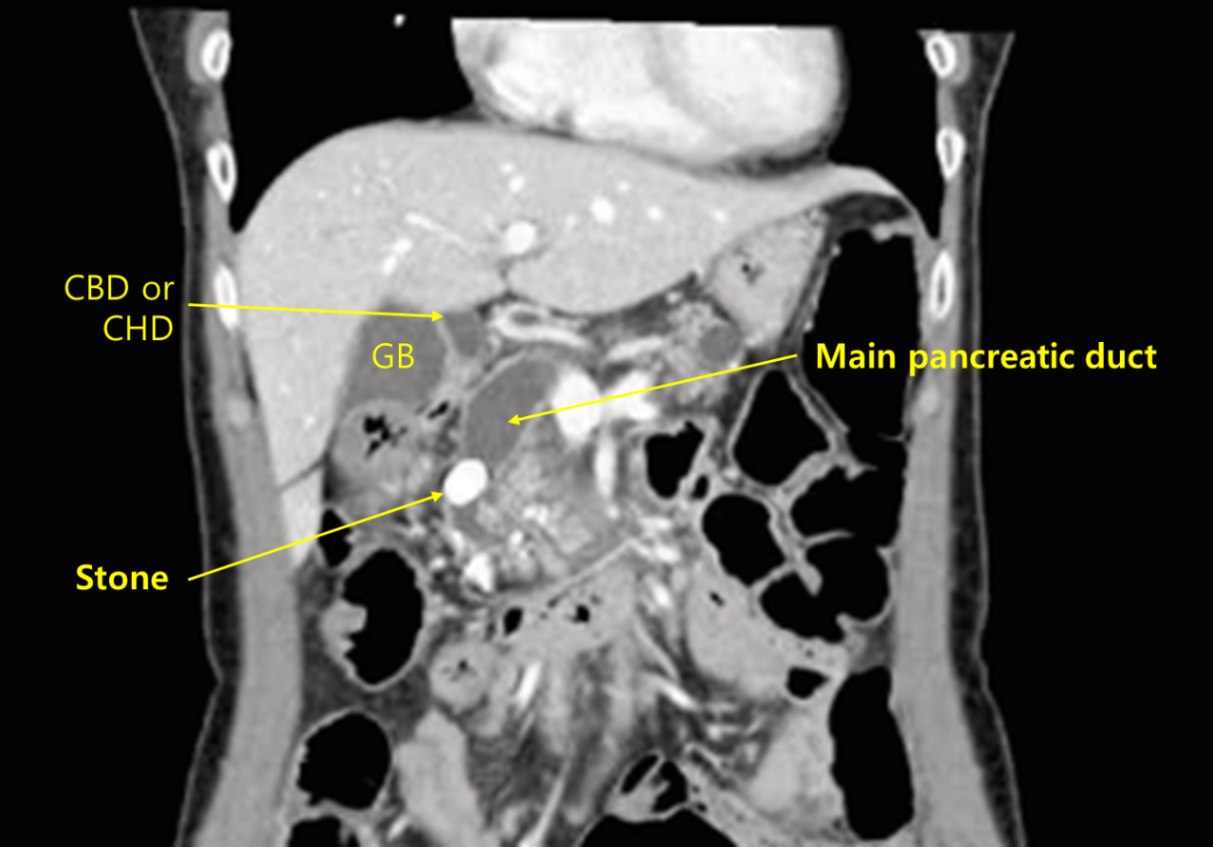

Img | CT: Large main pancreatic duct stone, causing upstream dilatation |

Imp: 총췌관담석증(main pancreatic duct stone)

CT상 main pancreatic duct stone이 확인되므로 ERCP with EST를 시행한다.

• 통증의 원인을 확인하기 위해 CT를 시행, CBD 중간에 매우 큰 stone이 확인되며, 이보다 상부로 dilatation이 확인된다. CT상 다른 cut이 주어지지 않아 upstream dilatation이 된 duct가 정확히 무엇인지 단언할 수는 없겠으나, T.bil/ALP가 정상인 점, GB와 intrahepatic duct의 dilatation이 없는 점으로 보아 CBD보다는 main pancreatic duct의 dilatation으로 추정된다.

• Main pancreatic duct stone에 대한 치료는 CBD stone에 대한 치료와 마찬가지로 endoscopic retrograde cholangiopancreatography(ERCP)를 시행하고, endoscopic sphincterotomy(EST)를 시행해 ampulla of Vater를 절개한 후 stone을 직접 물리적으로 빼내는 것이다.